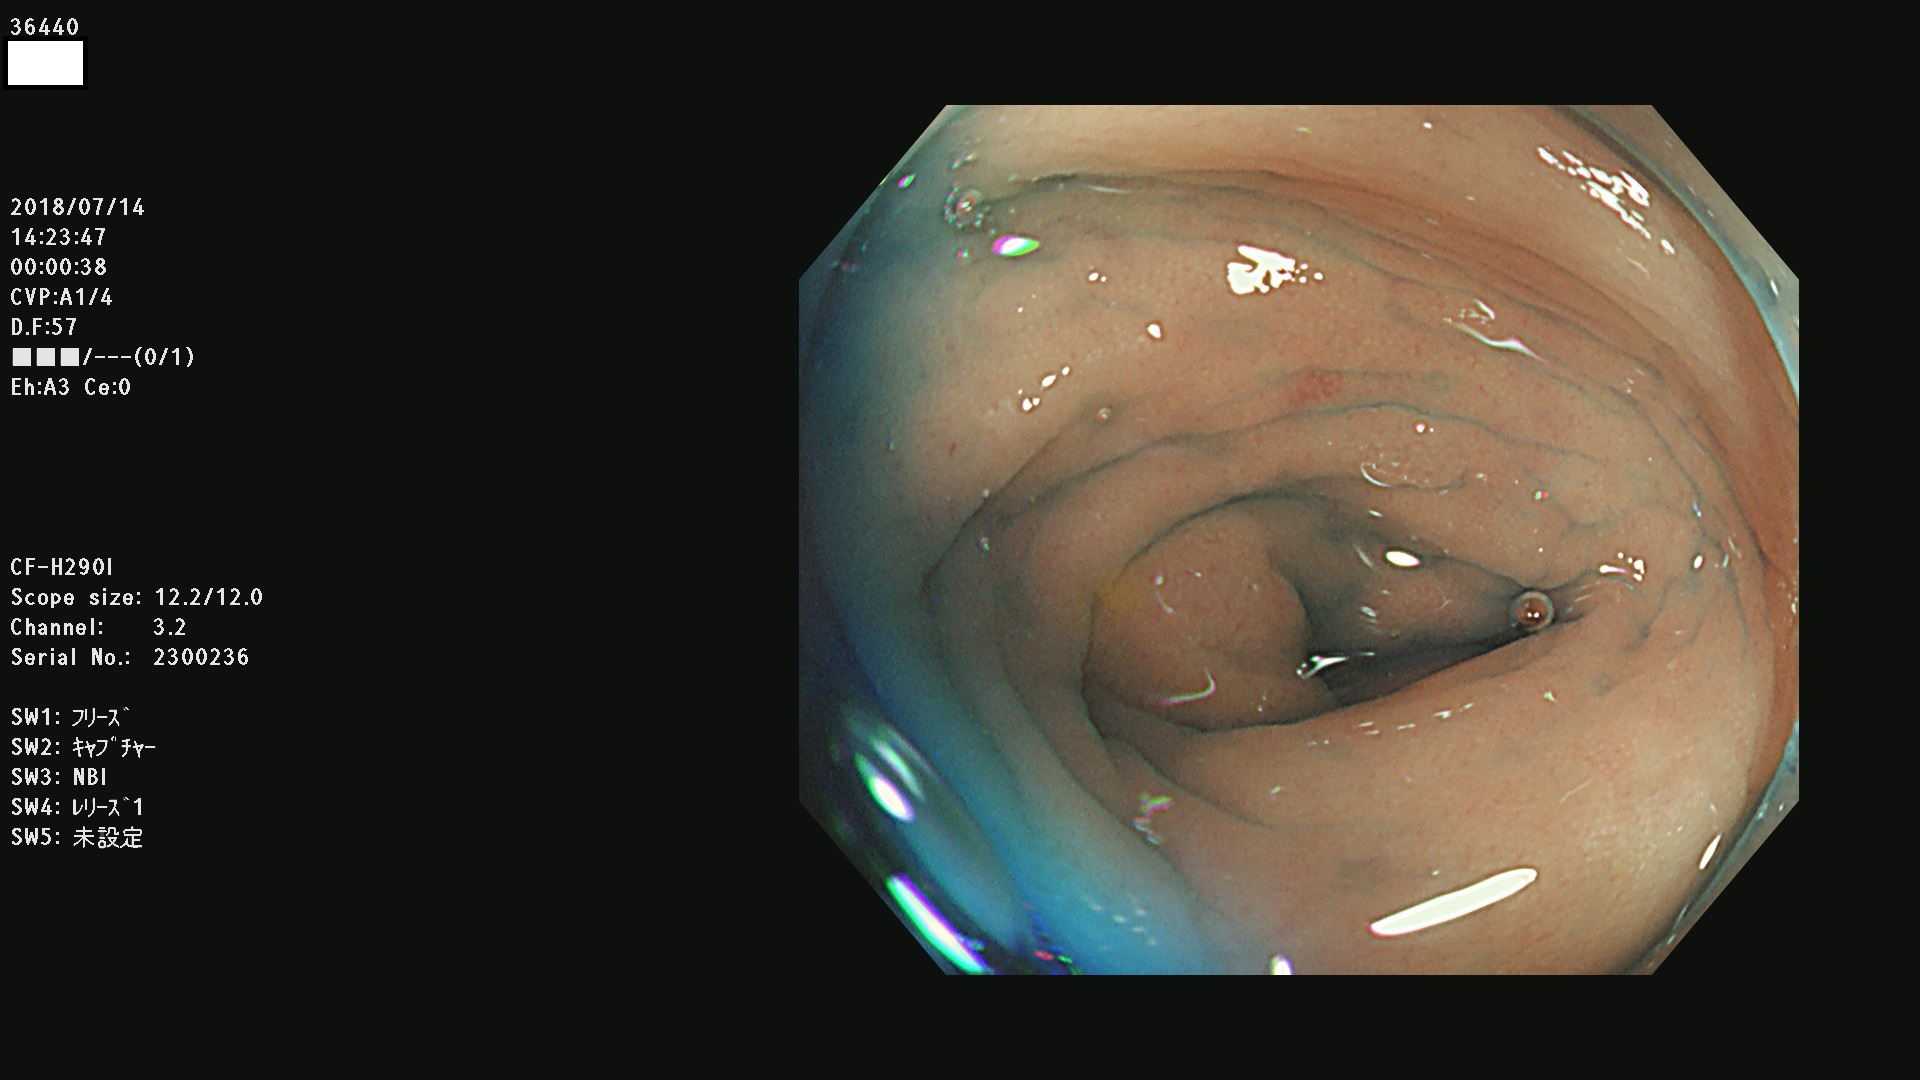

36400(SSAPのみ) 36402 36403 36404 36405 36406 36407 36408(SSAPのみ) 36412 36413 36414 36415 36416 36417 36418 36420 36422 36423 36424 36425 36426 36428 36429 36430 36431 36434 36435 36436 36437 36438 36440 36443 36447 36448 36449 36450 36452 36454 36458 36459 36460 36462(SSAPのみ) 36463 36464 36465 36466 36470 36471 36472 36473 36474 36475 36476 36478 36480 36481 36482 36484 36487 36488 36489 36490 36492 36494 36495 36496 36497 36498

発見困難で危険性の高い平坦型病変(上記100名より抽出)